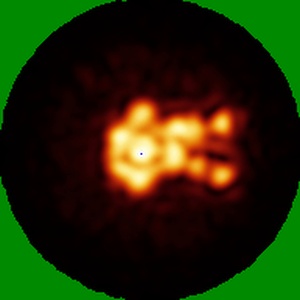

Rabbit 37496 base and gp41-GH epitope polyclonal Fabs in complex with BG505 MD39.3 SOSIP

Single-particle25.0 Å